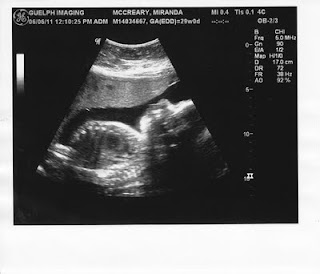

29 Weeks!!!!

Today is 29 weeks..... I got to see baby Squirt today!!!!! Boy is he getting big. (and yes it was confirmed, that he is still a he) I even got to see his scrotum, isn't that fantastic???? Hahaha..

Here are the two photos that were given to me today.

So he is nice and comfy in there.. In a wonderful position too.... Transverse... Bum down and straight across my stomach... That is how I figured he was.. His head is on my left side.... I did a little research and am not too concerned as there is TONS of time before he gets here to move into a nicer position because staying this way, is not going to be too pretty.....

The ultrasound Tech. could not give me any measurements, she said she was not allowed, but said my Dr. will have the ultrasound in 2-3 days. I do not have my next appointment with the OB until 2 weeks. Well anyways though, I know he is bigger, and he continues to grow... I just think he is going to be a "big" little guy!!!!!!